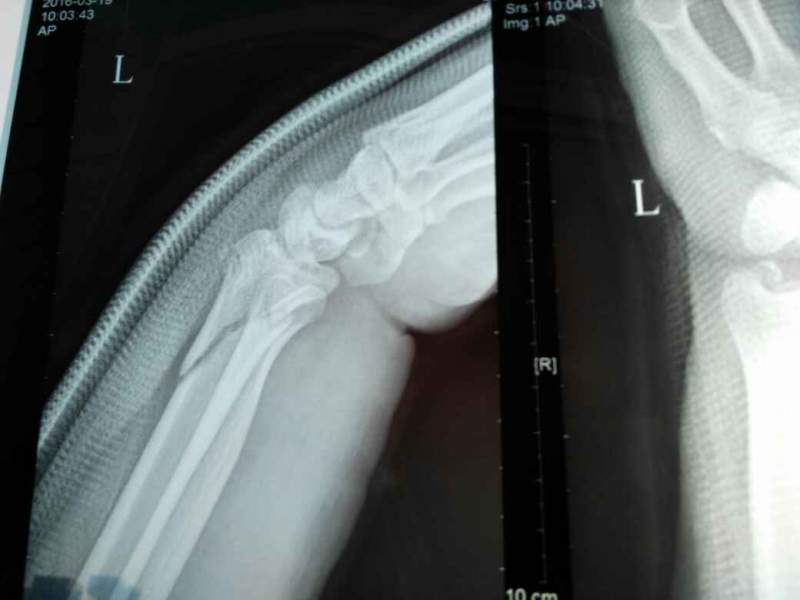

°Ö°Ö×óÊÖÍó¹ÇÕÛ£¬ÕâÊǸ´Î»Ö®ºóÅĵģ¬ÕâÔõôÑù£¿ ÒÑÓÐ3È˲ÎÓë

| ¸´Î»Í¦ºÃÁË£¬ºÃºÃÑø×žÍÐУ¬Ê¯¸à¹Ì¶¨4-6ÖÜ |

¶Ôλ¶ÔÏß¶¼Í¦ºÃ£¬¹Ì¶¨6ÖÜ£¬¼ÓÇ¿ÓªÑø ·¢×ÔСľ³æAndroid¿Í»§¶Ë |